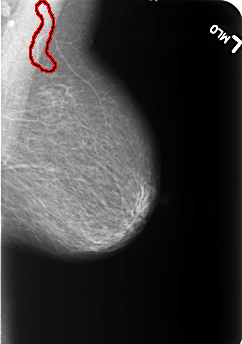

B_3233_1.LEFT_MLO

LEFT_MLO LINES 5496 PIXELS_PER_LINE 3872 BITS_PER_PIXEL 12 RESOLUTION 50 OVERLAY

FILE: B_3233_1.LEFT_MLO.OVERLAY

TOTAL_ABNORMALITIES 1

ABNORMALITY 1

LESION_TYPE CALCIFICATION TYPE VASCULAR DISTRIBUTION N/A

ASSESSMENT 2

SUBTLETY 4

PATHOLOGY BENIGN_WITHOUT_CALLBACK

TOTAL_OUTLINES 1